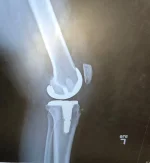

I am scheduled to have one of my knees replaced on 11/01/18.